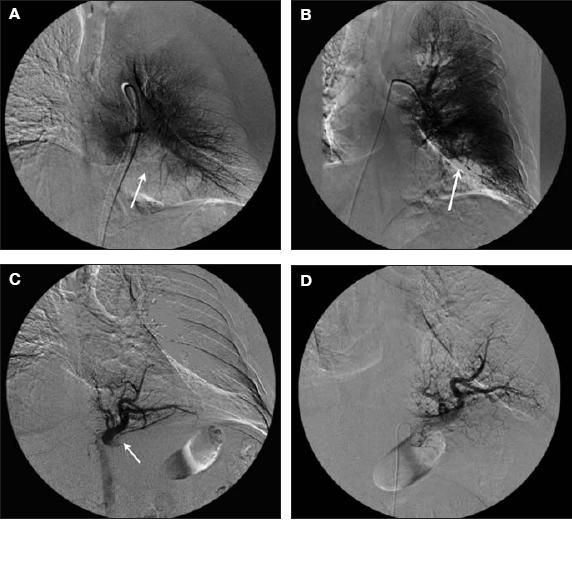

Figure 2 – Left pulmonary arteriogram shows a paucity of pulmonary arterial vessels in the left lung base posteromedially compatible with the posterior basal segment (A and B). Findings in the remainder of the left pulmonary arterial tree are unremarkable, without filling defects or other appreciable abnormality. No arteriovenous malformation or other abnormal arteriovenous shunting is identified. A descending thoracic aortogram shows the abnormal artery arising from the abdominal aorta just below the diaphragm, extending up into the basal portion of the left lung (C). A selective arteriogram of the aberrant sequestration artery shows a large vessel arising from the aorta extending up into the posteromedial and inferior portion of the left lung and filling of that segment of the lung that did not fill on the left pulmonary arteriogram (D).

• A left pulmonary arteriogram demonstrated a paucity of pulmonary arterial vessels in the left lung base posteromedially compatible with the posterior basal segment. Findings in the remainder of the left pulmonary arterial tree were unremarkable, without filling defects or other appreciable abnormalities. No arteriovenous malformation or other abnormal arteriovenous shunting was identified.

• A descending thoracic aortogram showed an abnormal artery arising from the abdominal aorta just below the diaphragm extending up into the basal portion of the left lung.

• A selective arteriogram of the aberrant sequestration artery showed a large vessel arising from the aorta extending into the posteromedial and inferior portion of the left lung and filling the segment of the lung that did not fill on the left pulmonary arteriogram. No significant arteriovenous shunting or abnormal communication between the artery and the draining left pulmonary vein was identified (Figure 3). No definite arteriovenous malformation was identified. The venous drainage was into the inferior left pulmonary vein.

• A descending thoracic aortogram more superiorly showed no other appreciable abnormalities.